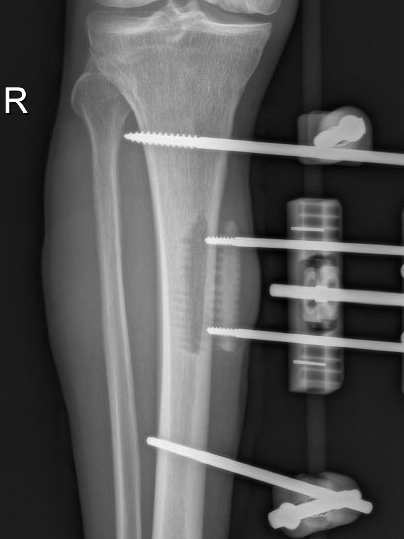

为提升区域内基层医疗机构糖尿病足诊疗服务能力、促进青年医师对糖尿病足的规范化诊治水平,遵义市第二城市医疗集团总院(贵州航天医院)圆满举办贵州省继续医学教育项目——胫骨横向骨搬移技术治疗糖尿病足专题研讨班。 贵州航天医院党委委员、副院长彭亮出席会议并致辞,遵义市第二城市医疗集团各成员单位,以及红花岗区、汇川区、绥阳县、桐梓县等多个区县的基层医疗机构骨干医师参加会议。 研讨班 本次研讨班以胫骨横向骨搬移技术在糖尿病足治疗中的应用为核心主题,围绕糖尿病药物治疗与生活方式管理策略、围手术期血糖精准调控要点、胫骨横向骨搬移技术典型病例深度解析、糖尿病足的临床分型与个体化治疗方案制定等临床实践中的热点与难点展开深入探讨,通过专题授课、案例研讨、互动交流等多元化形式,为参会者搭建了理论与实践结合的学习平台。 此次研讨班不仅为区域内基层医院搭建了学术交流与经验共享的平台,更对推动糖尿病足预防、诊断与治疗的规范化、系统化发展起到了积极作用,有效助力青年医师更新专业知识体系、提升临床技能,为进一步保障区域内糖尿病足患者的健康奠定了坚实基础。 贵州航天医院骨科专家简介 陈明勇 骨一科主任,副主任医师 临床擅长:从事创伤骨科工作约20年,对骨缺损、骨不连、骨肿瘤、肢体畸形等的肢体矫形重建及功能重建,慢性化脓性骨髓炎的根治治疗、糖尿病足的保肢治疗、快速康复理念(ERAS)下的老年骨折的诊治,四肢复杂骨折的诊治,四肢骨折等微创手术治疗具有丰富的临床经验。 2004年毕业于遵义医学院临床专业,曾在中国人民解放军总医院、广西医科大学第一附属医院、上海第六人民医院骨科进修。中国中西医结合学会骨伤科专业委员会横向骨搬移治疗糖尿病足及微血管网再生学组首届委员,遵义市医学会创伤分会常务委员。 瞿 晖 骨科党支部书记,骨二科主任,副主任医师 临床擅长:对骨科的常见病、关节外科、脊柱外科及运动医学疾病的诊治具有丰富的临床经验,熟练掌握骨科手术操作技术。 毕业于遵义医学院临床医学系,2005年前往广州中山大学第一附院骨显微医学部进修学习,2011年前往成都华西医院进修学习,并多次在省内外学习骨科相关知识,是中华医学会骨科分会会员。 赵小锋 中共党员,骨二科副主任,副主任医师 临床擅长:从事骨科临床工作11年,对骨科常见病、多发病诊疗有较为丰富的临床经验,擅长脊柱相关疾病诊断及治疗,尤其是颈、腰、腿疼痛疾病诊断及治疗,擅长胸腰椎骨折微创经皮穿刺内固定术、经皮穿刺椎体成形术、经皮穿刺脊柱内镜下腰椎间盘摘除术、单纯开创腰椎间盘摘除术、腰椎滑脱复位椎间植骨椎融合内固定术、腰椎管狭窄减压融合内固定术及人工髋、膝关节置换术等。 2012年毕业于遵义医学院外科学专业硕士研究生,2019年参加“遵义市115医学人才精英计划”于上海交通大学第一附属医院培训学习,2023年于北京大学第三人民医院脊柱外科进修学习,曾获得遵义市优秀医师荣誉称号。 遵义市手外科第一届委员,遵义市医学会创伤分会第一届委员,遵义市医学会创伤分会第二届委员,贵州省康复医学会第三届脊柱脊髓专业会委员,遵义市医学会烧伤与整形外科学分会委员,发表论文5篇,其中国家级核心期刊1篇,SCI论文1篇,主持市级课题1项并结题,参与市级课题2项。 赵兴东 骨科主任医师 临床擅长:擅长骨科的常见病及各种创伤、四肢骨折创伤修复、骨感染、手足疾病的诊治和手足体表畸形的矫形整复,熟练掌握骨科四肢骨病及创伤的手术操作技术,尤其在四肢关节复杂性损伤、手足外伤、组织缺损创面、难治创面的皮瓣修复方面及平足、高弓足矫形方面及四肢慢性疼痛诊治、康复方面具有丰富的临床经验。 硕士研究生,毕业于遵义医学院临床外科系,2015年前往山东省立医院手足外科进修学习;遵义市医学分会创伤分会第一、二届委员,遵义市手外科医学会第二委届员会常务委员;在省级及省级以上期刊发表文章9篇,参编著作2部,参与主持并完成市级课题1项,参与市级课题2项、省级课题1项。 张艳金 中共党员,骨科副主任医师 临床擅长:从事骨外科工作16年,对复合伤、多发伤的救治、四肢骨干骨折、关节周围骨折、骨肿瘤、骨髓炎等诊治具有丰富的临床经验。 中共党员,硕士研究生,2006年本科毕业于山西医科大学第二临床医学院,2011年研究生毕业于北京军区总医院;在“老年COPD患者合并髋部骨折的诊治”国际合作课题组研究两年,在老年髋部骨折的诊治方面具有丰富的经验,并发表论文6篇;主持遵义市级课题1项,承担遵义医科大学的临床教学工作,获得遵义医科大学优秀带教老师荣誉。编撰有《骨科疾病诊疗精粹》一书,开展2项新技术,编撰地方规范《务川自治县创伤骨科常见疾病诊疗规范》一书。 张俊凯 骨科副主任医师 临床擅长:从事骨科临床工作28年,对创伤骨折、骨感染、骨缺损、骨不连等外科诊治,四肢骨折的微创手术治疗,四肢复杂骨折(如关节内粉碎性骨折、多发骨折等)的损伤控制及手术治疗等具有丰富的临床经验。 1995年毕业于遵义医学院临床专业,2009年前往复旦大学附属医院骨科进修1年。 卢懿明 中共党员,骨科副主任医师 临床擅长:从事骨科工作18年,对创伤骨折、四肢骨折的微创手术治疗、四肢复杂骨折(如关节内粉碎性骨折、多发骨折等)的损伤控制及手术治疗,尤其是髋部骨折的PFNA等微创技术,踝关节骨折、膝关节周围骨折的Mipo微创技术等具有丰富的临床经验,开展了4项新技术,发明6项新型专利技术。 2005年毕业于遵义医学院临床专业,2017年,前往南方医科大学第三附属医院骨科进修半年,回院后运用Mipo技术对骨干骨折及干骺端骨折的治疗技术,同时积极开展骨盆骨折、髋臼骨折腹直肌外侧切口的应用;发表了多篇专业论文,经常参与省内外学术交流会授课,获得医院荣誉称号多个。 邬夏荣 骨科副主任医师 临床擅长:从事骨科工作16年,对四肢复杂骨折、骨肿瘤的诊治,尤其是足踝创伤、慢性踝关节损伤、平足症等诊疗具有丰富的临床经验。 2006年毕业于遵义医科大学临床医学专业,曾在陆军军医大学西南医院进修学习,发表多篇骨科学术论文。 余德怀 中共党员,骨科副主任医师 临床擅长:从事骨科工作10余年,对运动医学、骨关节、脊柱外科常见病、多发病的诊治具有丰富的临床经验。 硕士研究生,2011年毕业于遵义医学院临床医学专业,曾前往遵义医科大学附属医院运动医学专业进修学习;是贵州省医学会运动医学分会青年委员,西部关节镜联盟委员;发表多篇骨科学术论文。 冯 乾 骨科副主任医师 临床擅长:从事骨科工作近20年,熟练掌握骨科多发病及常见病的诊治,尤其对脊柱退变性疾病的诊断及治疗具有丰富的临床经验,主要研究脊柱微创相关治疗方式,能熟练开展椎间孔镜及UBE。 曾前往北京大学第三医院进修学习疼痛及椎间孔镜、首都医科大学友谊医院专业进修脊柱内镜;是贵州省康复医学会第三届脊柱脊髓专业委员会委员;发明专利3项、发表脊柱外科专业论文多篇。 贵州航天医院骨科简介 基本情况 贵州航天医院(原3417医院)骨科组建于1968年,前身是以创伤和断肢(断指)再植闻名于世的上海市第六人民医院骨科,中国断肢(断指)再植的奠基者、中科院院士陈仲伟等专家莅临科室指导医疗和教学,并在70年代开展了贵州省首例断肢(断指)再植手术。组建50余年来,诊治患者已逾百万,挽救了无数的伤病员,成为了保障遵义地区人民群众健康的重要支撑。 经过几代人的不懈努力,今天的骨科,已由创伤骨科发展至骨病、骨肿瘤、骨结核等领域,现有脊柱外科、关节外科、四肢创伤、手足外科四个亚专科,成为了集医疗、教学、科研于一体的综合学科,是贵州省临床重点专科、遵义市临床重点专科、遵义市骨科临床医学中心、遵义市基层骨科专科联盟理事长单位。 科室目前开放床位110张,共有医护人员50余人,副高级以上专家18人,硕士研究生15人。拥有一流骨科医疗设备多台,每年不定期选派优秀技术骨干到全国各大知名医学院校进修、学习、参观、交流,并邀请国内、国外知名专家教授来院进行交流、指导,通过不断引进国内外先进的诊疗技术,科室医疗技术水平稳步提升,为广大人民群众提供了优质的医疗服务。 专科特色 骨一科 (一)骨缺损、骨不连的肢体与功能重建 胫骨横向骨搬移技术治疗糖尿病足: (二)慢性骨髓炎的根治治疗 (三)肢体缺血性疾病如糖尿病足、脉管炎的保肢治疗 (四)皮瓣修复 (五)复杂创伤的治疗 (六)老年髋部骨折及小儿骨折快速手术 老年髋部骨折: 骨二科 (一)胸腰椎骨折微创经皮椎弓根螺钉固定术 (二)老年性骨质疏松性患者腰椎滑脱脊柱内固定术(骨水泥螺钉) (三)V形双通道脊柱内镜技术(VBE)腰椎融合术治疗腰椎退行性疾病 (四)老年性骨质疏松性骨折(PVP/PKP)术 (五)人工髋关节置换术 (六)双侧股骨头坏死人工全髋关节置换 (七)右侧全髋置换术后假体周围骨折翻修 (八)人工膝关节置换术 (九)人工膝关节假体松动翻修 (十)关节镜技术 传统手术切口 关节镜技术切口 诊疗范围 骨一科 1.四肢创伤、矫形。 2.手、足踝外科。 骨二科 End